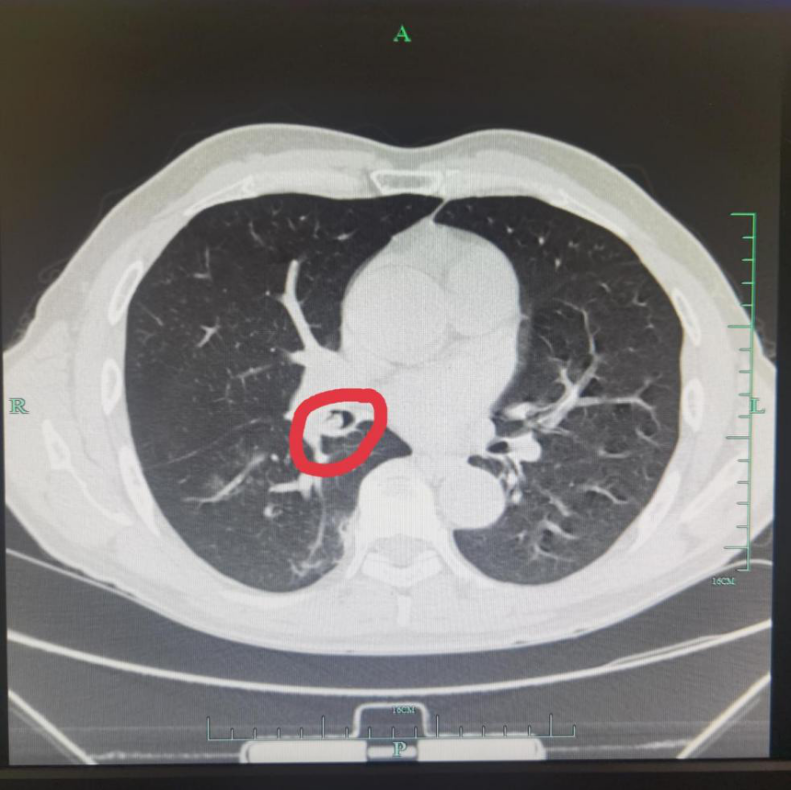

接诊的沈晓强副主任医师仔细询问病情后,立即给吴先生安排了胸部CT检查,结果提示:右下支气管内可及高密度影,异物考虑。

△胸部CT:右下支气管开口处可及高密度影